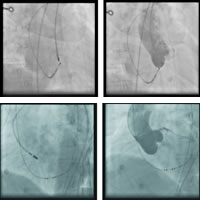

图7 消融靶点位置X线影像图(左前斜位及右前斜位)

图8 无冠窦内消融终止心动过速

经电解剖标测和CT成像(CARTO-merge,图6)、主动脉根部造影(图7)证实,最早激动点位于无冠窦,在此处予以盐水灌注(35W,45℃)17ml/min,消融房速即刻终止(图8),猝发刺激及静脉滴注异丙肾上腺素未诱发任何心动过速。